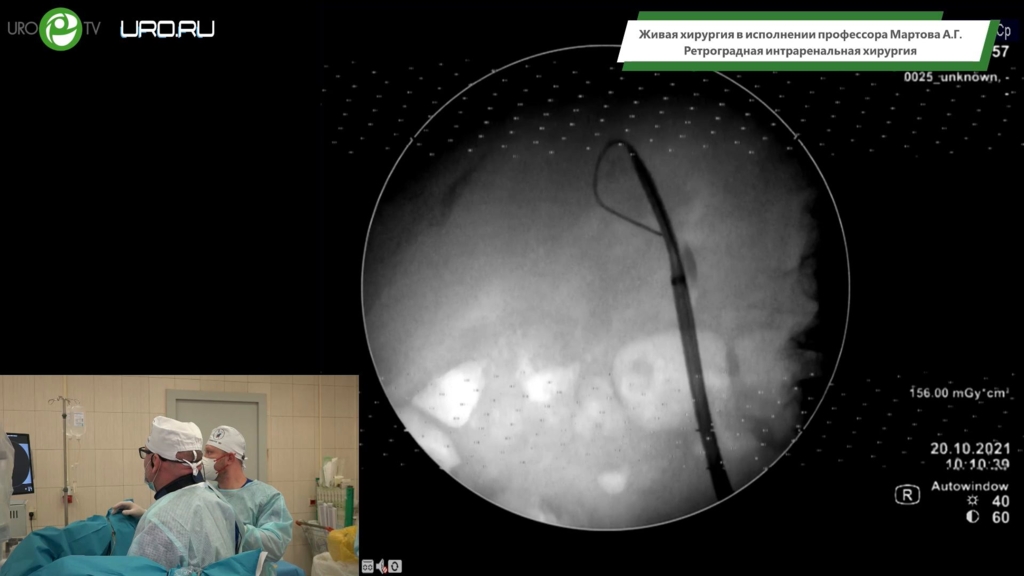

Мартов А.Г. - Ретроградная интраренальная хирургия

03 ноя 2021

Мочекаменная болезнь